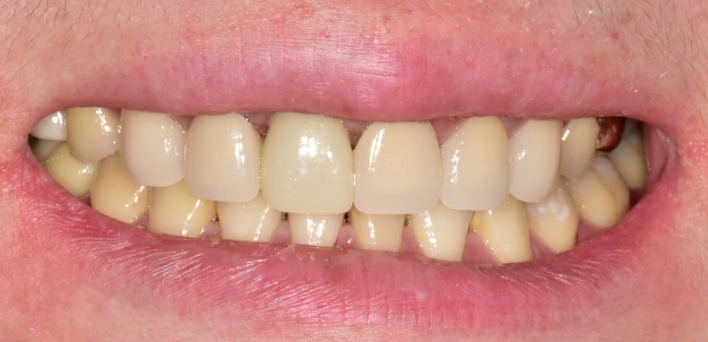

임플란트 : 손 ** 님 (50대)

치아가 있다는게, 아직도 정말 꿈만 같아요.

Before Before

2020.02.30

After After

※ 더서울치과의원은 의료법을 준수하며 위 케이스는 실제 환자의 동의를 얻은 사례로 치료 전, 후가 동일한 환경에서 촬영되었습니다.

환자 케이스에 따라 부작용이 발생할 수 있습니다. 이 부분은 의료진의 충분한 상담과 체크를 통해 예방하고 줄일 수 있습니다.

[임플란트 부작용] 수술 후 관리가 소홀할 경우 출혈, 주위염 등의 부작용이 발생할 수 있어 구강 위생을 철저히 유지하고, 정기적인 검진을 통해 상태를 점검하는 것이 중요합니다.

환자 특징

환자 특징01무치악 상태

환자 특징02수년간 무치악으로 지내심

임플란트가 불가능할것이라

생각하고 내원

위, 아래 6개씩 식립

디지털 풀아치 임플란트